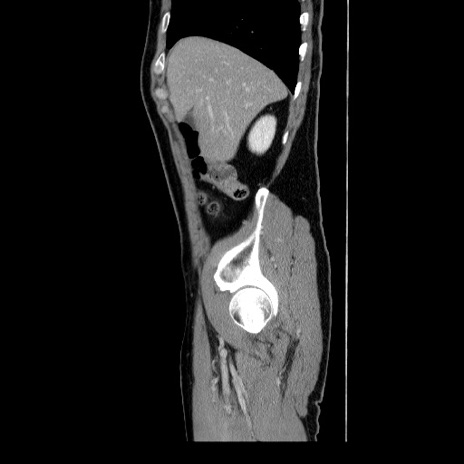

冠状断像

【症例】60歳代 男性

【主訴】右鼠径部膨隆

【現病歴】1年程前より右鼠径部膨隆あり。自己にて還納可能だったため放置していた。3時間前より右鼠径部の脱出を認め、還納困難となり受診。

【身体所見】右鼠径部に小児頭大の膨隆あり。弾性硬であり、用手還納は困難。左鼠径部にも膨隆を認める。脱出はなし。